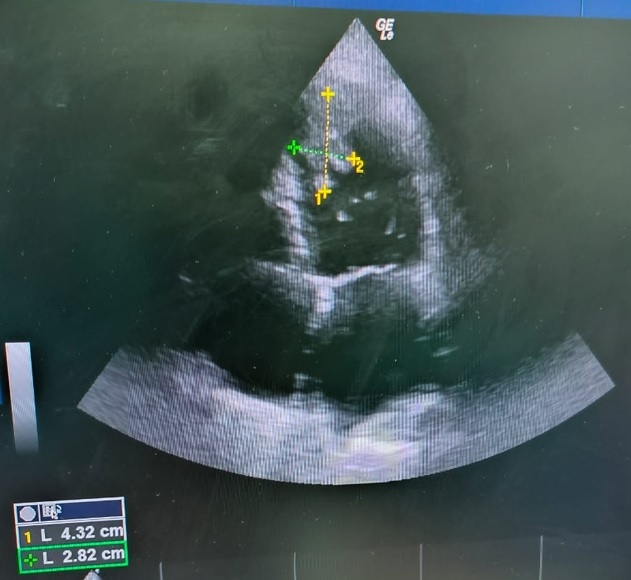

一名患有缺血性心肌病的42岁男性出现急性双侧股动脉栓塞。在对双侧股动脉进行栓子切除术和筋膜切开术后,经胸超声心动图检查发现左心室(LV)有两个梗阻性高流动性血栓。考虑到手术风险,建议采用抗凝治疗而不是手术。然而,出血风险阻碍了抗凝治疗的继续,导致血栓增大。患者随后出现多器官功能衰竭和弥散性血管内凝血病,最终不治身亡。我们还系统地查阅了 PubMed 和 Scopus 数据库中的左心室有蒂血栓病例,分别检索到 74 篇和 63 篇报道。其中,37篇相关报道(45例)加上人工检索的11篇报道被纳入数据提取,除我们的病例外,共有56例。根据病因和风险,左心室血栓是可以预测和预防的,尤其是在缺血性事件后。一旦确诊,需要明确的诊断算法和警惕的随访以及多学科管理。

A 42-year-old male with ischemic cardiomyopathy presented with acute bilateral femoral artery embolization. After management with embolectomy and fasciotomy in both femoral arteries, transthoracic echocardiography revealed two pedunculated highly mobile left ventricle (LV) thrombi. Given the procedural risk, anticoagulation therapy was recommended over surgery. However, the bleeding risk impeded the continuation of anticoagulation, which increased the thrombus size. Multiorgan failure and disseminated intravascular coagulopathy followed and the patient died. We also systematically reviewed the PubMed and Scopus databases for pedunculated LV thrombi cases and retrieved 74 and 63 reports respectively. Of these, 37 relevant reports (45 cases) plus 11 reports from the manual search were included for data extraction, a total of 56 cases besides our case. Based on the etiologies and risks, LV thrombi are predictable and preventable, especially after ischemic events. A clear diagnostic algorithm and vigilant follow-up are needed as well as multidisciplinary management once a diagnosis is confirmed.